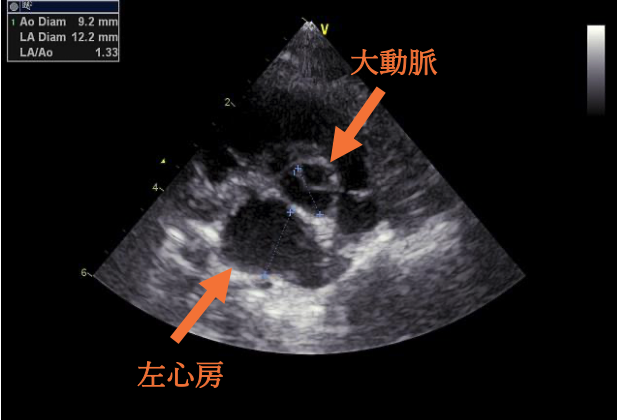

今回の心臓超音波検査では、左心室の壁が厚くなり、大動脈に血液を送り出す出口が少し狭くなっていることが確認されました。ただし、ねこちゃんには症状がなく、検査上でも重度ではなかったため、今回はお薬を使わずに経過観察となりました。

肥大型心筋症とは、左心室の壁が厚くなってしまい、血液をうまく送り出せなくなる病気です。